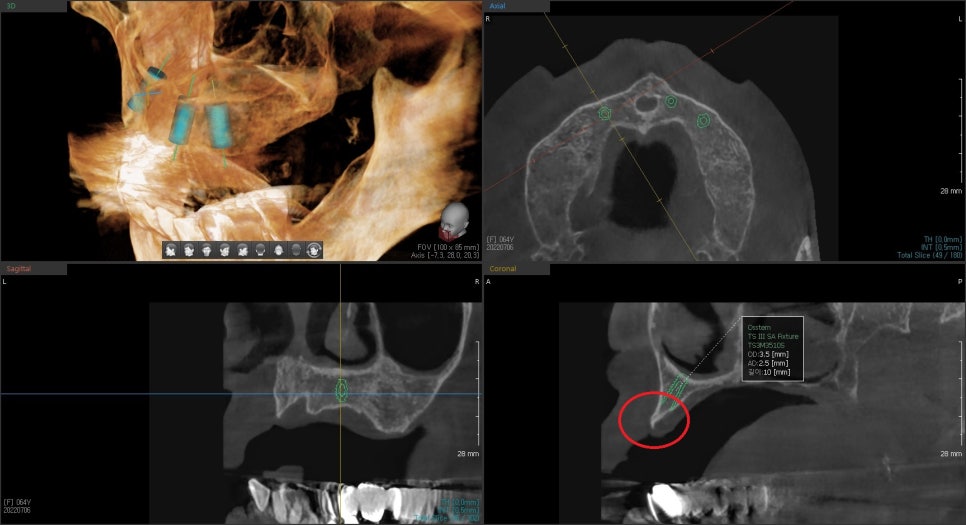

CT를 찍어본 사진은 뼈가 흡수되고 있었습니다.

임플란트의 위치, 갯수, 방향을 위해 시뮬레이션을 해보았습니다.

뼈의 끝부분이 뾰쪽해지면서 임플란트를 식립하기 위해서는

상부의 골을 다듬고 임플란트 식립후

치조골이식술을 통해 임플란트 주변 골의 두께를 충분히 확보해 주는것이 좋습니다.